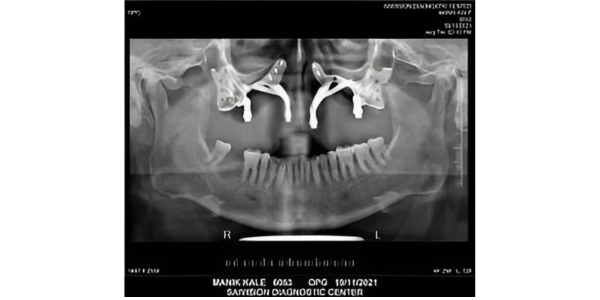

Ms. Mr Manik Kale, a 47-year-old male,

residing at Pune had to undergo

Maxillectomy due to Mucormycosis leaving

a large defect on his maxilla.

Dr. J B Garde leading Oral and Maxillofacial Surgeon, Implantologist, HOD of OMFS Dept. at M.A.Rangoonwala Dental College, Advanced Dental Clinic, and Pune along with our design team planned the implant design virtually via zoom platform.